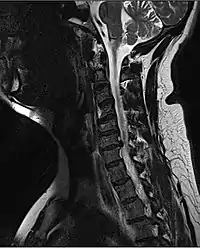

![]() МРТ перелому шийного відділу зі зміщенням зі здавленням спинного мозку. МРТ перелому шийного відділу зі зміщенням зі здавленням спинного мозку. | |

Рентгенографічна оцінка за допомогою рентгенографії, КТ або МРТ може визначити, чи є пошкодження хребта й де вони локалізуються. Найбільш доступними зазвичай є рентгенівські знімки [73] , які можуть виявити нестабільність або нерівність спинного стовпа, але не дають дуже детальних зображень і можуть пропустити травми спинного мозку або зміщення зв'язок або дисків. Таким чином, коли результати рентгенографії є нормальними, але спинальну травму все ще підозрюють через біль або симптоми випадіння чутливості чи рухів, використовують КТ або МРТ. [73] КТ дає більше деталей, ніж звичайна рентгенографія, але більше опромінює пацієнта [74], й до того ж, усе ще не дає зображень спинного мозку й міжхребцевих зв'язок. МРТ найбільш детально показує структури тіла і є стандартом при виявленому неврологічному дефіциті. [75]